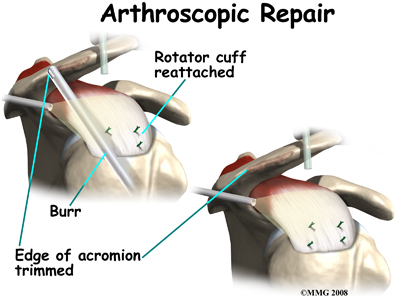

There are many small instruments that have been specially designed to perform surgery in the joint. Some of these instruments are used to remove torn and degenerative tissue. Some of these instruments nibble away bits of tissue and then vacuum them up from out of the joint. Others are designed to burr away bone tissue and vacuum it out of the joint. These instruments are used to remove any bone spurs that are rubbing on the tendons of the shoulder and smooth the under surface of the acromion and AC joint.

Once any degenerative tissue and bone spurs are removed, the torn rotator cuff tendon can be reattached to the bone. Special devices have been designed to reattach these ligaments. These devices are called suture anchors.

Suture anchors are special devices that have been designed to attach tissue to bone. In the past, many different ways were used to attach soft tissue (such as ligaments and tendons) to bone. The usual methods have included placing stitches through drill holes in the bone, special staples and screws with special washers – all designed to hold the tissue against the bone until healing occurred. Most of these techniques required larger incisions to be able to see what was going on and to get the hardware and soft tissue in the right location.

Today, suture anchors have simplified the process and created a much stronger way of attaching soft tissue to bone. These devices are small enough that the can be placed into the appropriate place in the bone through a small incision using the arthroscope. Most of these devices are made of either metal or a special plastic-like material that dissolves over time. This is the “anchor” portion of the device. The anchor is drilled into the bone where the surgeon wished to attach the soft tissue. Sutures are attached to the anchor and threaded through the soft tissue and tied down against the bone.